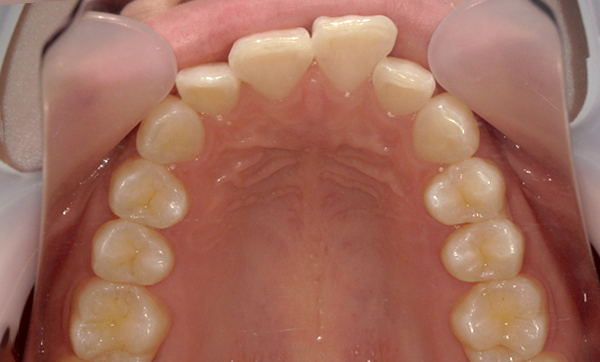

症例_008 「上下の前歯」症例

治療期間:13ヶ月金額:57万円+税40代女性捻転歯前歯のガタガタ

Before | After |

---|---|